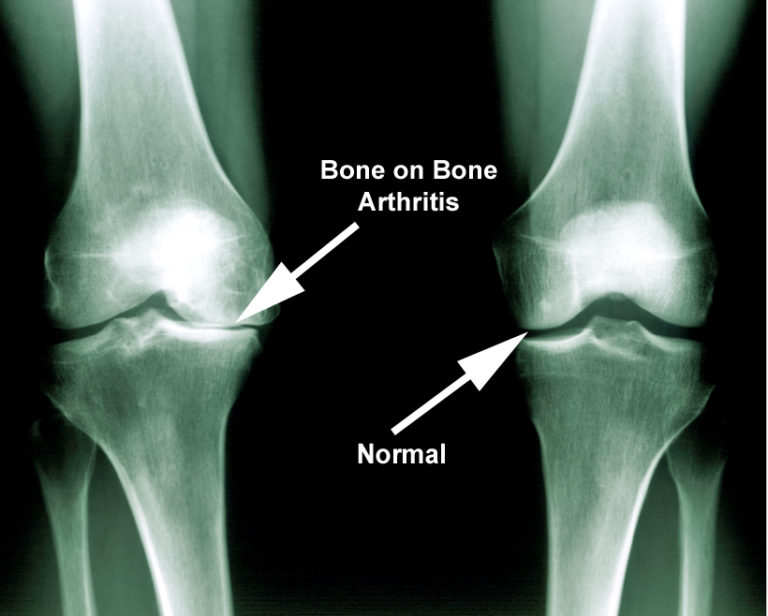

What Does Arthritis Look Like? Can Arthritis Be Removed From A Joint Arthritis can cause symptoms like joint pain, stiffness, and swelling. If arthritis causes serious damage to the joints, a person may require surgery. The surgeon takes out the diseased parts of your bones and replaces them with an. Arthritis surgery can help fix or replace a damaged joint, reduce pain, and improve the way the joint functions. These types of. Can Arthritis Be Removed From A Joint.